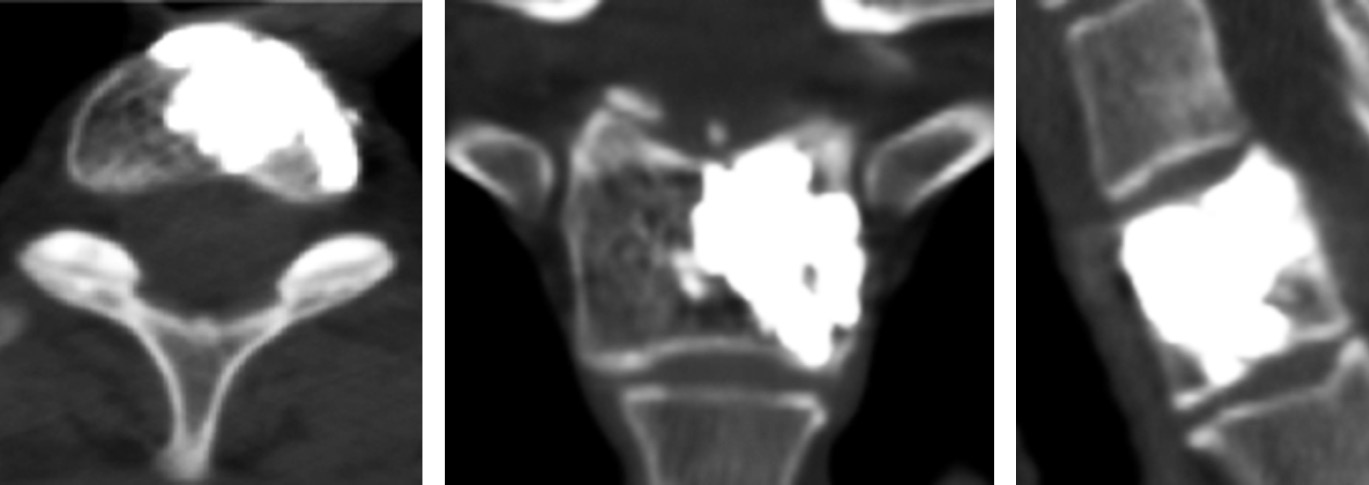

The patient was hospitalized in the in-patient facility where he underwent open PV of the vertebral body C7. After the surgery, complete regression of pain syndrome was registered. No unplanned migration of polymethyl methacrylate was detected in the postoperative CT images (Fig. 2).

Fig. 2. CT scans of vertebra C7 of patient A. after the surgery

The efficiency of PV was evaluated as per the clinical data of complete regression of pain syndrome (up to 0 points as per the VAS in both patients). After the surgery, both patients underwent a check-up CT examination. On CT images, the completeness of filling the cavity with hemangiomas with bone cement was visualized, from 86% to 94% of filling. The duration of hospital stay was 2–4 days. Subsequent CT control was performed after 6 months, and the absence of relapsing growth of hemangiomas was confirmed.